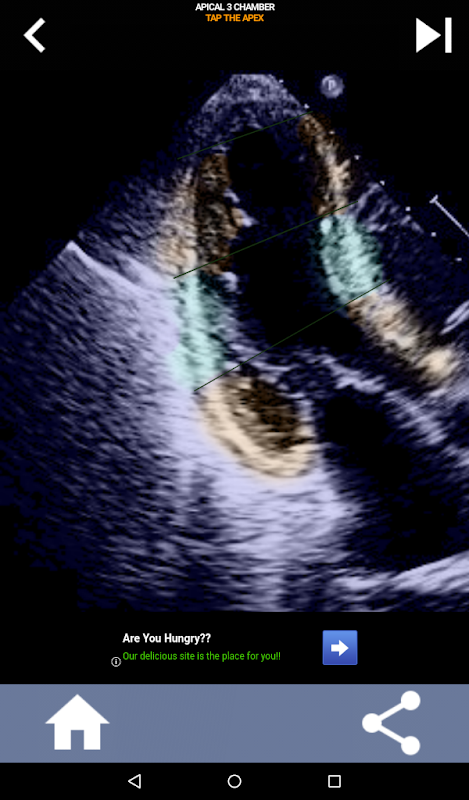

Abordagem visual baseada em questionário para aprender os segmentos cardíacos da AHA: ecocardiografia

Este aplicativo testará seu conhecimento usando imagens de eco reais, que geralmente considero o melhor método de ensino.